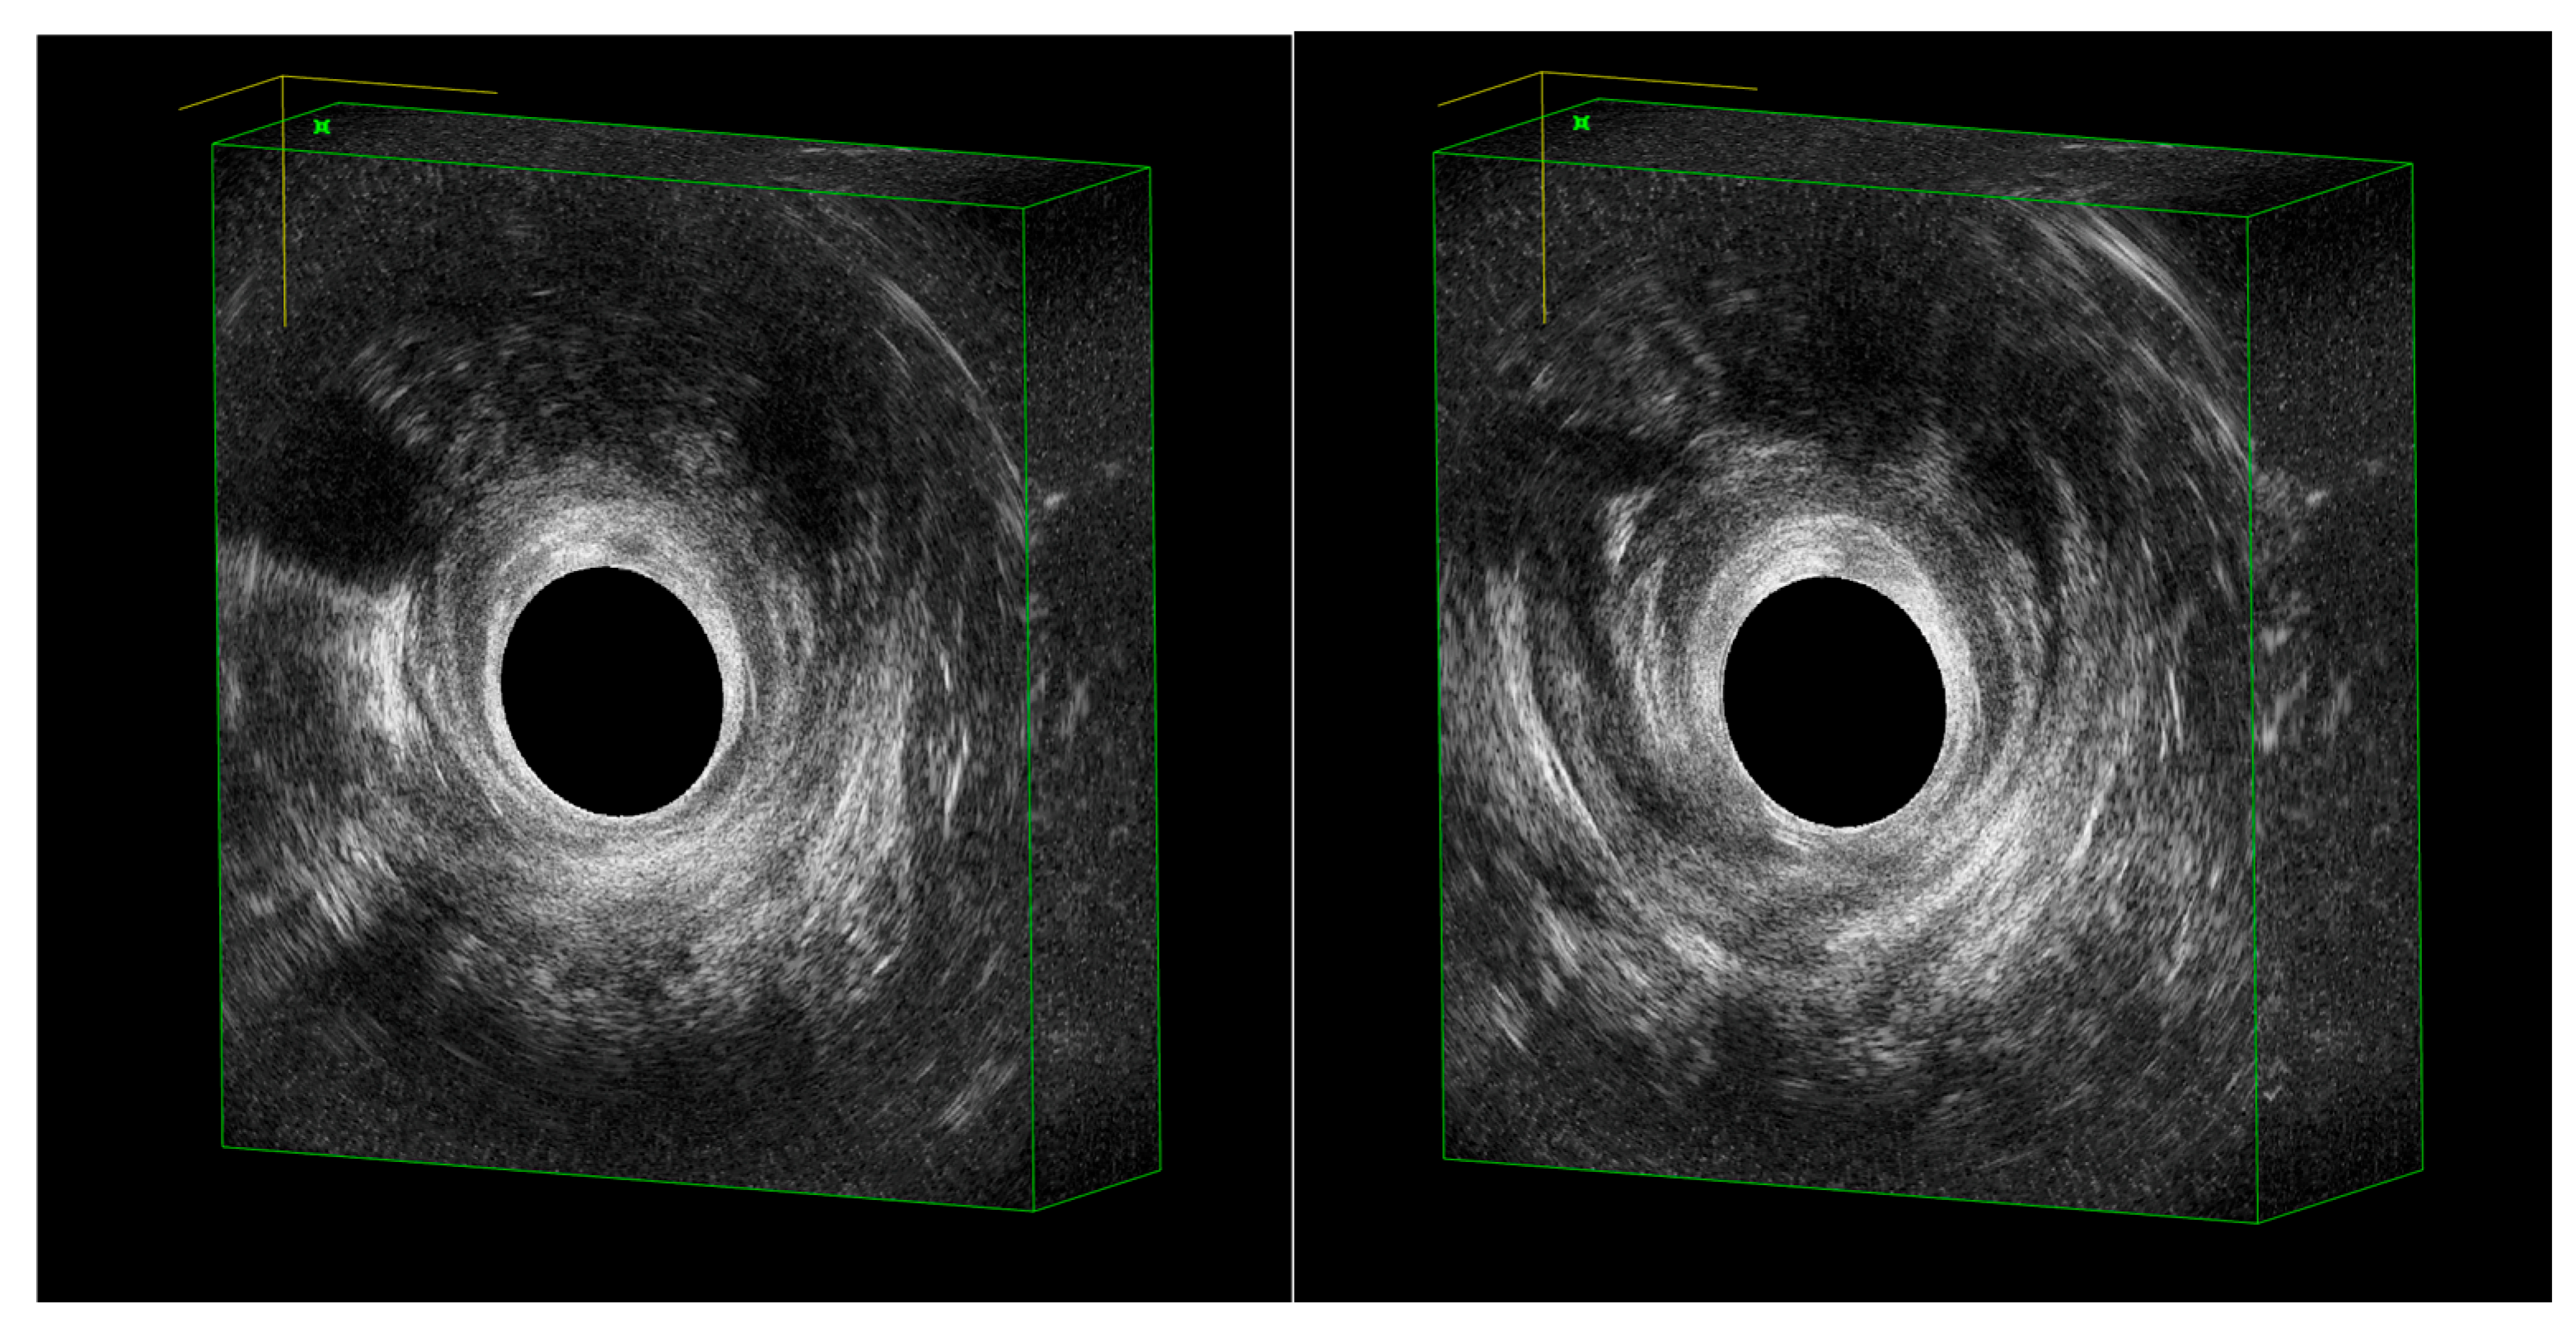

2. EAUS Technique

- Cho, H.-M.; Kye, B.-H.; Lee, Y.-S.; Yoo, N. Standardizing the 3D-Endoluminal Ultrasound Procedure: Optimal Delineation of Anorectal Anatomy. J. Surg. Ultrasound 2024, 11, 7–17. [Google Scholar] [CrossRef]